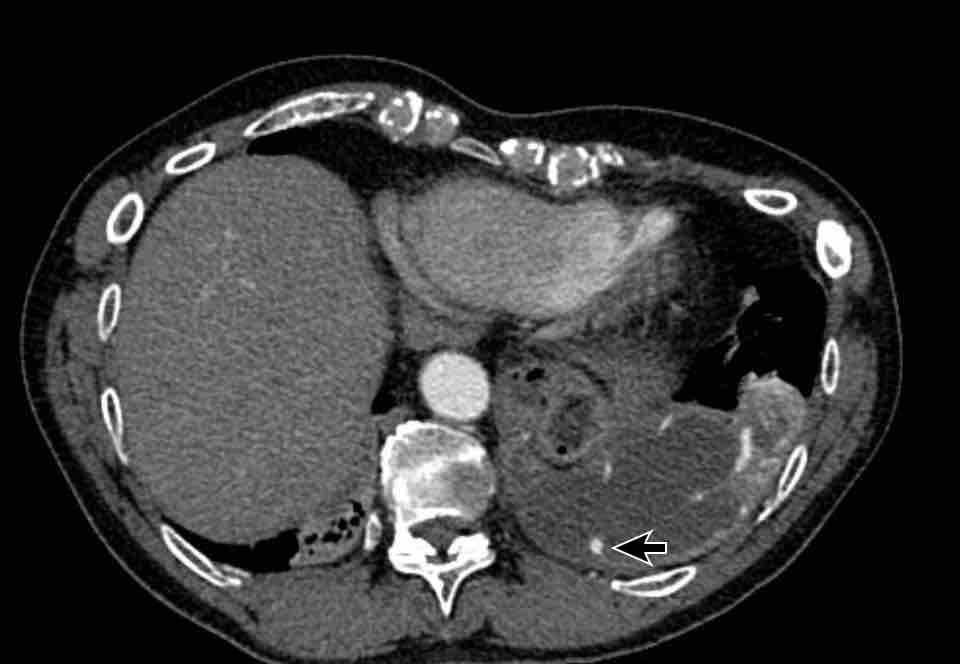

Hình ảnh

Bệnh nhân này được lên kế hoạch cắt thùy trên phải do ung thư phổi và bất thường mạch máu này ban đầu đã bị bỏ sót trên hình ảnh CT.

Những hệ quả trong phẫu thuật của bất thường như vậy nhấn mạnh tầm quan trọng của việc không bỏ sót các biến thể này.

PAPVR bên trái phát hiện tình cờ với dẫn lưu trên tim của máu từ thùy trên trái vào tĩnh mạch tay đầu trái (các mũi tên).